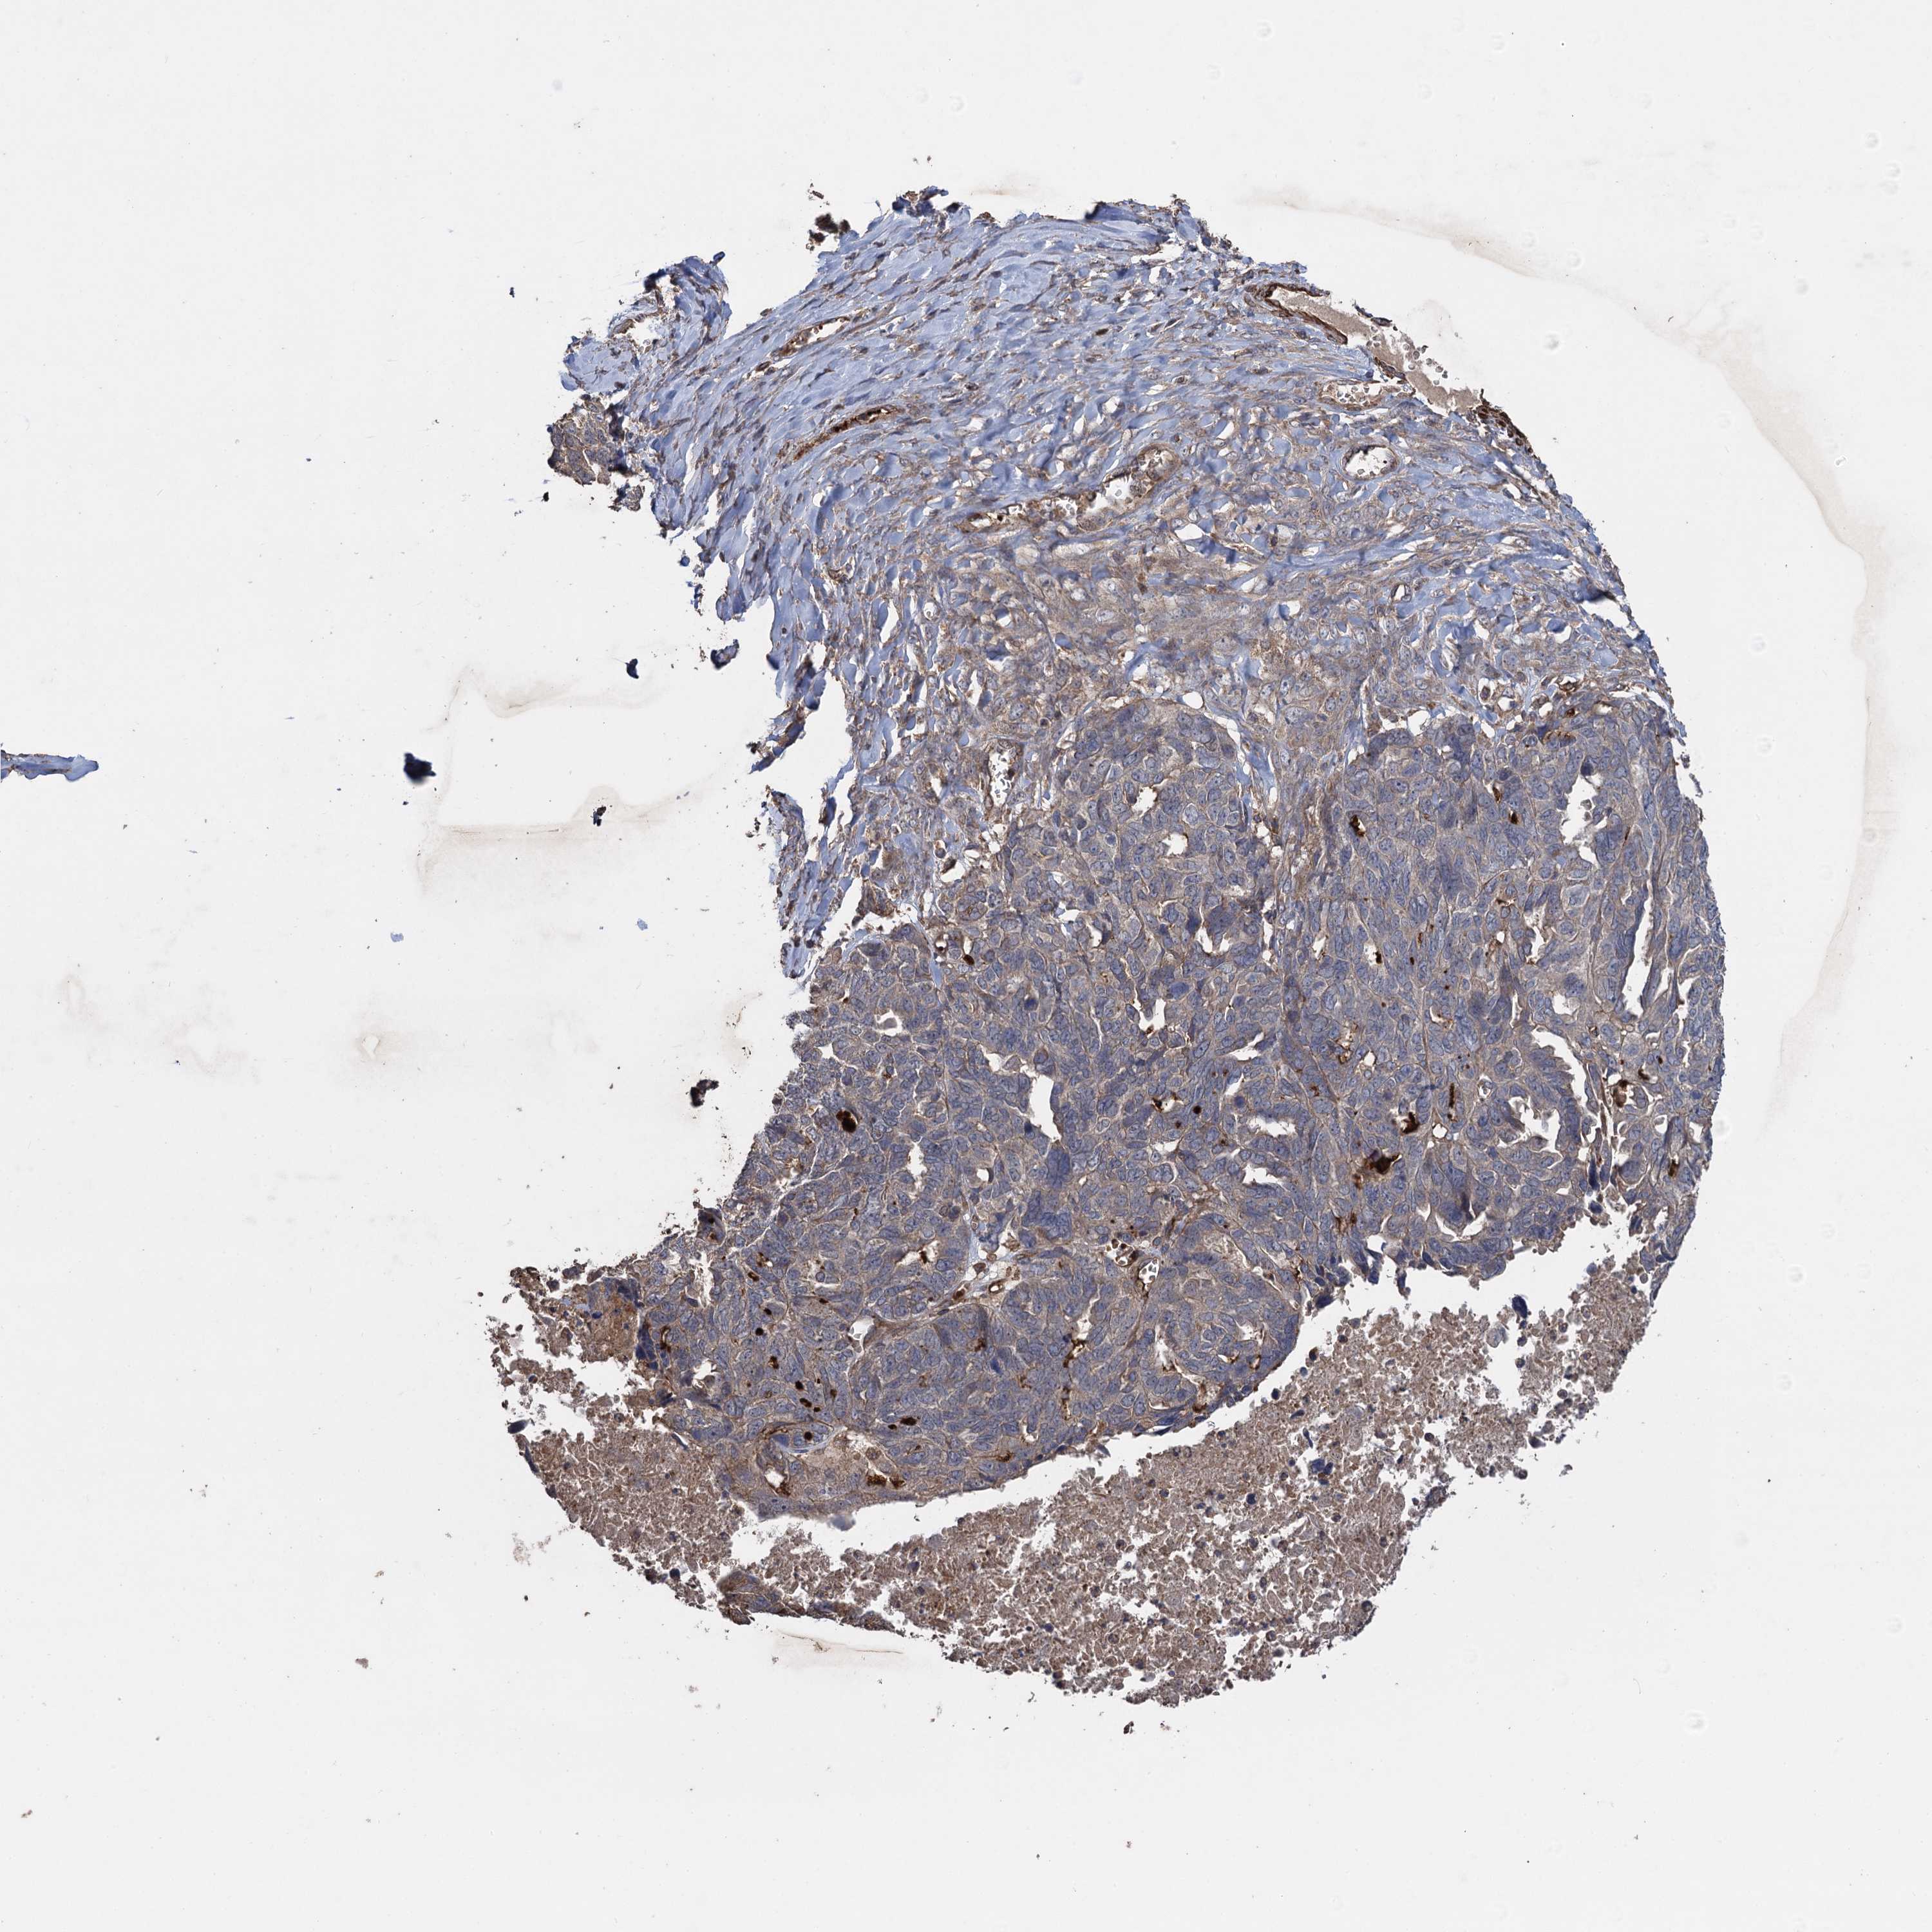

OVARIAN CANCER - Protein expressioni

A mouse-over function shows sample information and annotation data. Click on an image to view it in a full screen mode. Samples can be filtered based on level of antibody staining by selecting one or several of the following categories: high, medium, low and not detected. The assay and annotation is described here.

Note that samples used for immunohistochemistry by the Human Protein Atlas do not correspond to samples in the TCGA dataset.

Antibody stainingi

Antibody staining in the annotated cell types in the current human tissue is reported as not detected, low, medium, or high, based on conventional immunohistochemistry profiling in selected tissues. This score is based on the combination of the staining intensity and fraction of stained cells.

Each image is clickable and will lead to virtual microscopy that enables deeper exploration of all samples and also displays staining intensity scores, fraction scores and subcellular localization as well as patient and tissue information for each sample.

Antibody HPA041174

Antibody HPA041390

Carcinoma, endometroid